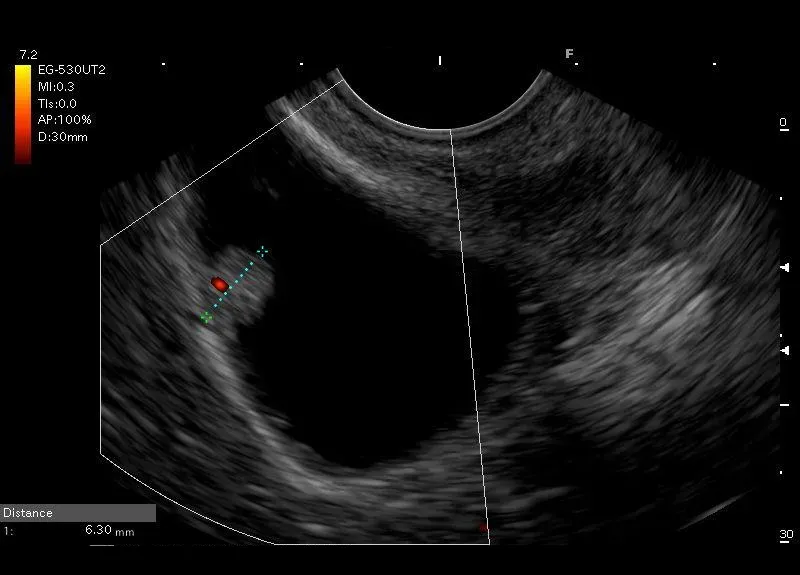

Owalna struktura  przylegająca do ściany pęcherzyka żółciowego, z widocznym przepływem naczyniowym w opcji Power Doppler w podstawie zmiany, bez cienia akustycznego, która nie zmieniła swojego położenia podczas próby wstrząsania- polip pęcherzyka żółciowego